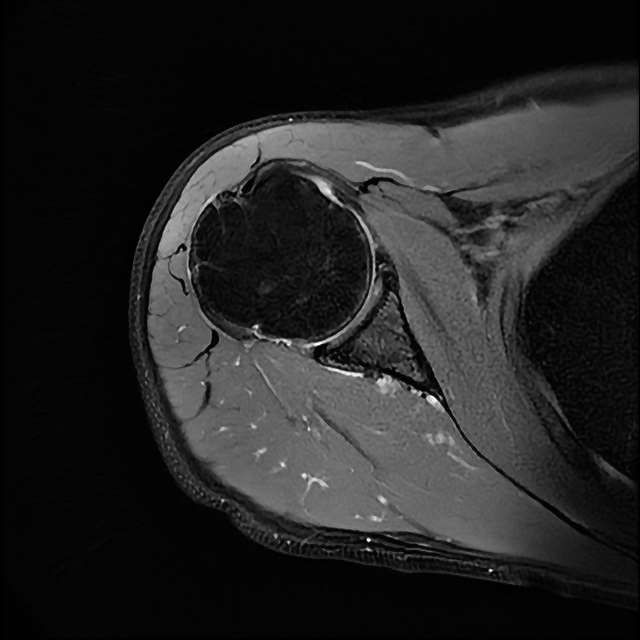

오른쪽 어깨 와순파열 및 점액낭염이 보인다고 하는데 상태를 알고 싶습니다

MRI 사진상 와순파열 점액낭염 등이 있다고 하는데..심한 상태인가요?

MRI상 와순파열, 회전근개 부분파열 등이 있으며 일부 염증소견이 있습니다.